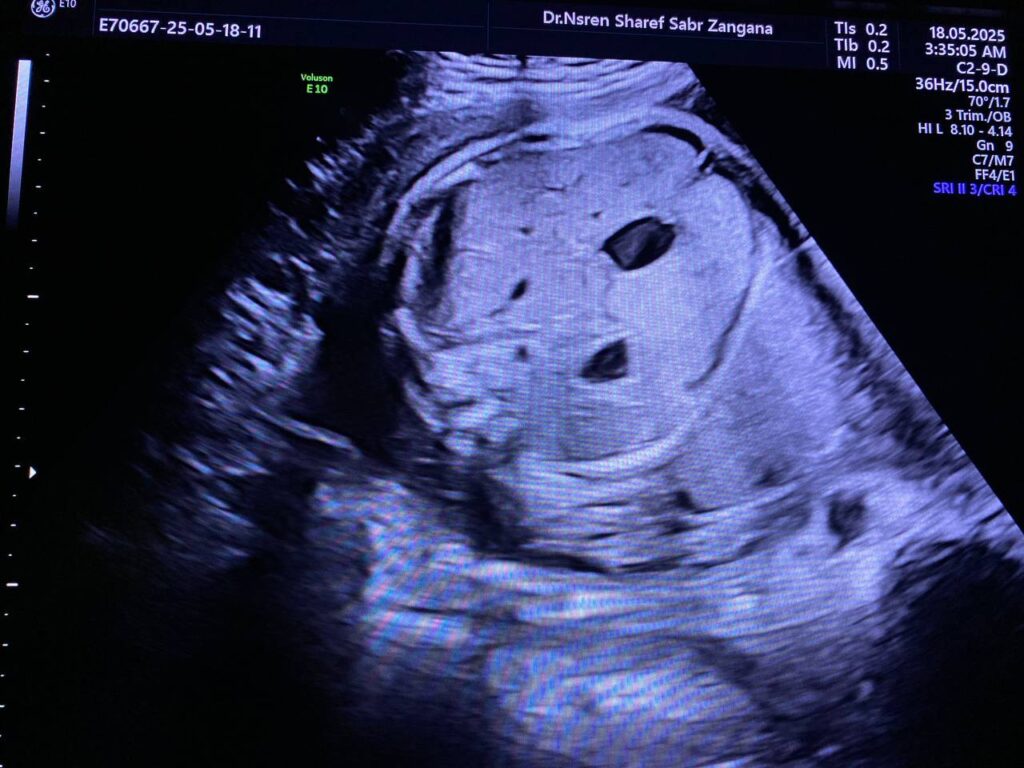

At 29wk pregnancy

Focal aneurysm dilatation of the hepatic umbilical vein 16 in length , 12mm in diamter.

And with Increase in amount of liquor. Amniotic fluid index = 30cm AC =80% , Hepatomegally ?